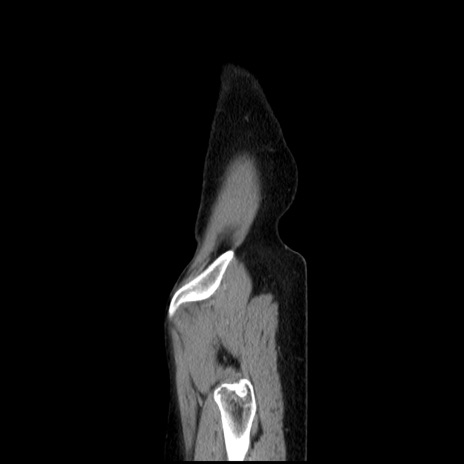

症例32(矢状断像)

【症例】40歳代 女性

【主訴】上腹部痛、嘔気・嘔吐

【現病歴】約9時間前頃から急に上腹部痛、嘔気、嘔吐が出現。改善しないため救急要請。

【既往歴】子宮頚癌(広汎子宮全摘術、放射線療法)、腸閉塞

【身体所見】腹部:平坦、軟、腸雑音亢進、上腹部を中心に腹部全体に圧痛あり。

【データ】WBC 8400、CRP 0.03